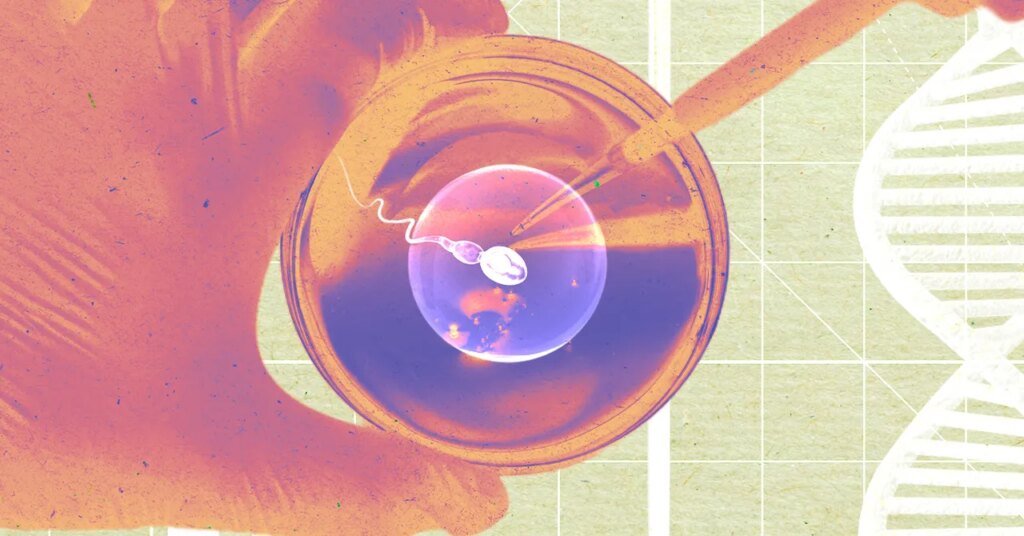

Pastuszak says early testing exhibits the lab-made sperm look “successfully an identical” to naturally made sperm. The process just isn’t but prepared for use to start out pregnancies, although. Paterna created embryos as an early take a look at to validate that its lab-made sperm was truly viable. The corporate plans to conduct a bigger, extra complete examine involving males with infertility. Paterna will extract sperm from their ejaculate or testicular tissue and use its methodology to generate sperm for the lads. From there, the corporate will use each the extracted sperm and lab-made sperm to fertilize eggs within the lab, evaluate fertilization charges between the 2 teams, and analyze the ensuing embryos for bodily and genetic abnormalities.

Paterna’s expertise is designed to exchange that course of, as an alternative taking a small biopsy of testicular tissue in a health care provider’s workplace. That tissue could be despatched to Paterna, which might carry out in vitro spermatogenesis. The corporate plans to cost someplace between $5,000 and $12,000 for the process.